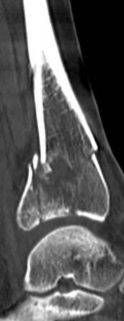

Fig 2.2-3a–h A CT scan with 3D reconstruction.

a–d Sagittal (a–b), coronal (c), and axial (d) images demonstrate displaced posterior, anterolateral, and medial fracture fragments resulting in intraarticular step and gap. The incongruent tibiotalar joint is best appreciated on the sagittal scan.

e–h The 3D reconstructed images show the external fracture anatomy and general alignment.